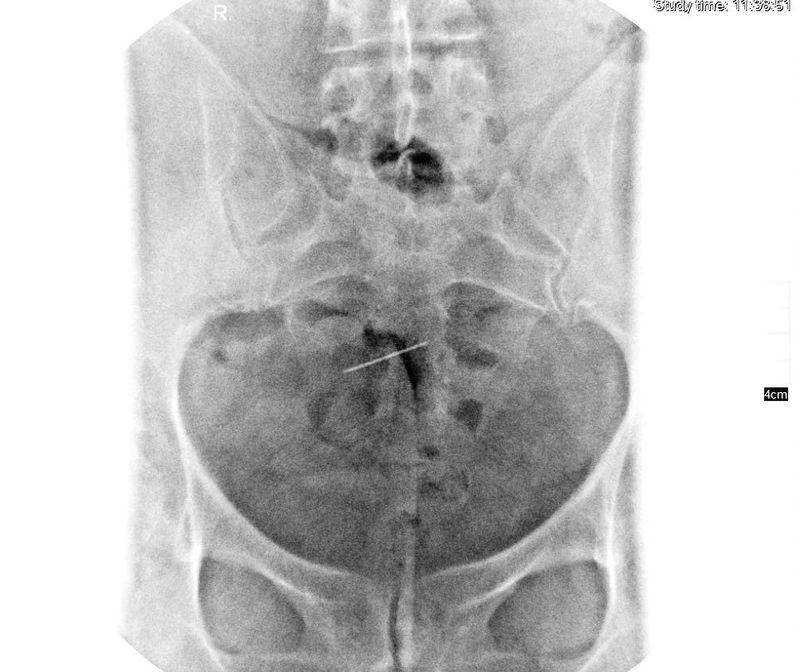

Femeia a fost dusă la spitalul Sf. Spiridon, acolo unde cadrele medicale care au îngrijit-o au descoperit „un ac medical care a migrat între oasele bazinului”.

Chinul femeii a început în anul 1990, atunci când a fost operată din cauza unei sarcini extrauterine cu peritonite. În timpulintervenției chirurgicale, dr. Doina Ianca, de la Maternitatea „Elena Doamna”, i-a extirpat o trompă și un ovar, dar a uitat un ac în abdomenul pacientei. Femeia a început să se simtă rău, din senin, după mai mulți ani.